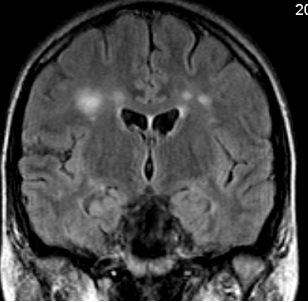

- T1W image + iv. contrast material (enhancement is seen in the right ponto-cerebellar angle: Schwannoma.)